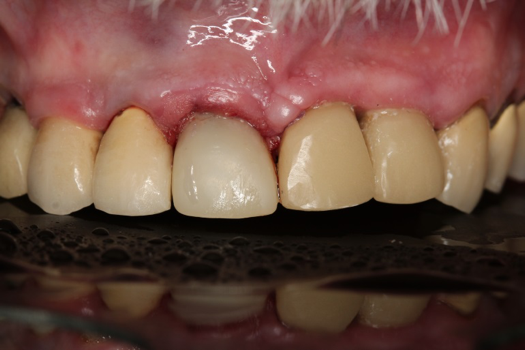

After 4 months of healing and integration of the bone around the implant, the digital workflow was initiated to develop the abutment and treatment plan. Another analog impression was made with an impression post and polyvinyl impression. The laboratory scanned the impression and digitized it to create the emergence profile of the milled titanium abutment and the final restoration (Figure 10 and Figure 11). The patient had a considerably thick soft-tissue profile, allowing a milled titanium abutment. The decision to use a titanium abutment was based on the patient's occlusion and propensity to fracture teeth or restorations. The virtual model was gray because the scanner does not recognize the color of the analog impression. The virtual final abutment and crown were approved and fabrication completed. The final restoration met the patient's esthetic values and his ability to function (Figure 12 and Figure 13).

Fig 12. Six months after cementation.

Figure 12

Fig 13. Radiograph 6 months after cementation.

Figure 13